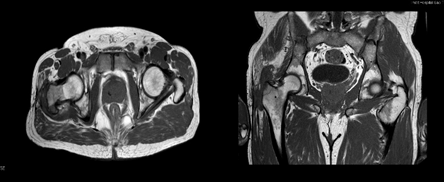

Figure 2 & 3 Axial and coronal MRI image: Intraosseous edema of the right greater trochanter, inflammatory phenomena of the soft tissues.

The MRI performed revealed signal changes in the bone marrow in the region of the right greater trochanter, compatible with intraosseous edema. Soft tissues adjacent to the greater trochanter with signs compatible with local inflammatory phenomena. Small infratrochanteric liquid collection with approximately 20 mm in longest axis. Analytically, a CRP of 1.24 mg/dl and positive Gamma interferon stood out, while other studies of autoimmune and infectious diseases, such as brucellosis, HIV, hepatitis or syphilis, were negative. It was decided to perform a new right trochanteric bursectomy and curettage with sequestrectomy, having found a large amount of fibrotic and devitalized tissue.